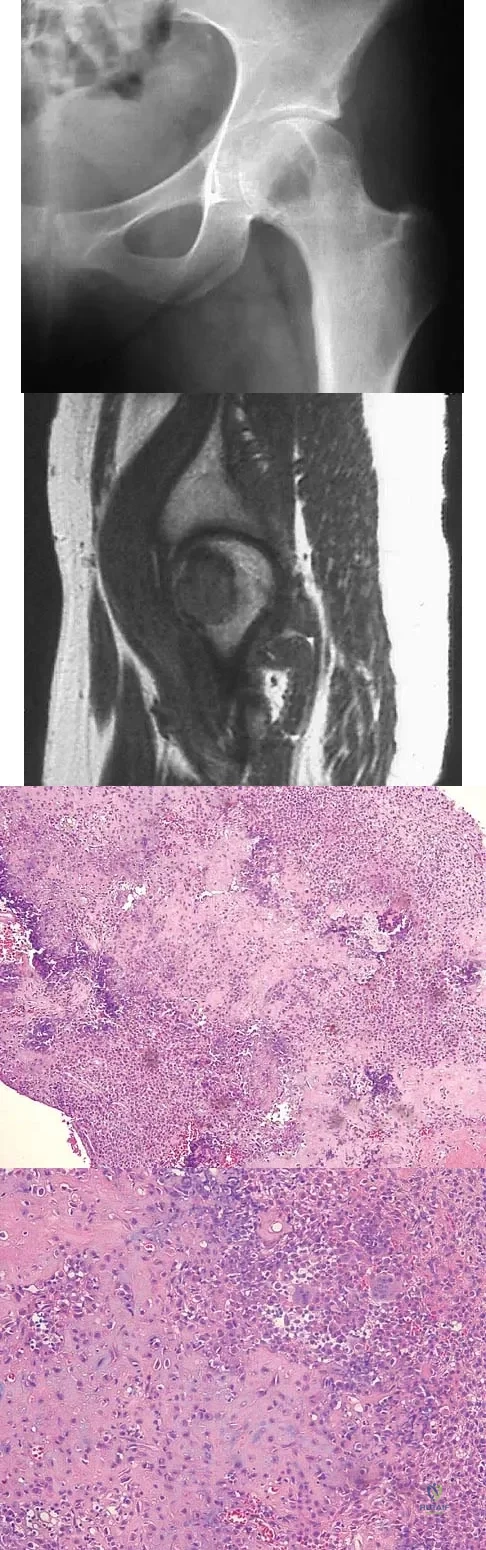

Question 100

A 16-year-old girl has had pain in the left groin for the past 4 months. She notes that the pain is worse at night; however, she denies any history of trauma and has no constitutional symptoms. There is no history of steroid or alcohol use. Examination reveals pain in the left groin with rotation of the hip. There is no associated soft-tissue mass. A radiograph and MRI scan are shown in Figures 32a and 32b, and biopsy specimens are shown in Figures 32c and 32d. What is the most likely diagnosis?

Explanation